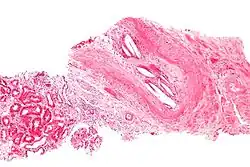

| Micrograph showing a cholesterol embolus in a medium sized artery of the kidney. Kidney biopsy. H&E stain. | |

The microscopic examination of tissue (histology) gives the definitive diagnosis. The diagnostic histopathologic finding is intravascular cholesterol crystals, which are seen as cholesterol clefts in routinely processed tissue (embedded in paraffin wax).[7] The cholesterol crystals may be associated with macrophages, including giant cells, and eosinophils.

The sensitivity of small core biopsies is modest, due to sampling error, as the process is often patchy. Affected organs show the characteristic histologic changes in 50-75% of the clinically diagnosed cases.[3][5] Non-specific tissue findings suggestive of a cholesterol embolization include ischemic changes, necrosis and unstable-appearing complex atherosclerotic plaques (that are cholesterol-laden and have a thin fibrous cap). While biopsy findings may not be diagnostic, they have significant value, as they help exclude alternate diagnoses, e.g. vasculitis, that often cannot be made confidently based on clinical criteria.